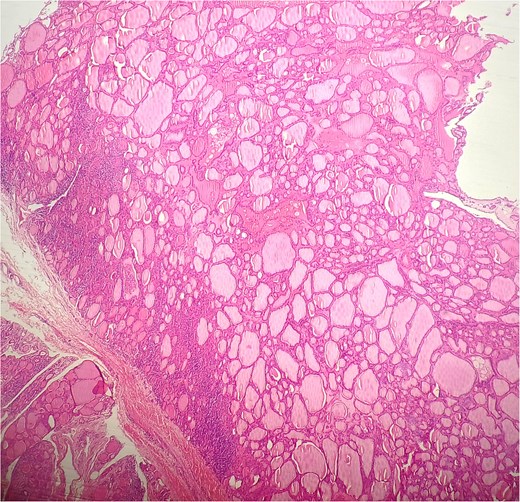

A 47-year-old woman with unremarkable medical history, presented with a 2 months history of neck mass along the midline. Physical examination revealed a 6 cm mobile, thyroid nodule without compressive symptoms. There was no associated erythema, fluctuance, tenderness or adhesion to adjacent structures. There was also no associated cervical lymphadenopathy. The rest of the physical exam was unremarkable. Laboratory tests including TSH, FT3, and FT4 revealed normal levels. On cervical ultrasound, there were a 62 mm left toto-lobar nodule classified as EU-TIRADS3, and an 11 mm right nodule, also classified as EU-TIRADS3. Fine-needle aspiration cytology concluded to a benign lesion classified as BETHESDA II. The patient reported respiratory discomfort in the supine position, leading to the indication for a lobectomy. Gross examination of the specimen revealed a toto-lobular nodule with a colloid appearance. It was well-circumscribed by a thin and regular fibrous capsule. The nodule measured 4 × 6 cm and exhibited areas of fibrous, whitish remodeling, as well as hemorrhagic and cystic changes. On microscopic examination, the nodule corresponded to a macro vesicular adenoma altered by fibrosis and hemorrhage. It was surrounded by a thin, regular, and intact fibrous capsule. However, at the periphery of the nodule, adjacent to the thyroid pseudo capsule, a 1.2 cm cystic ductal structure was observed. It showed pseudostratified ciliated columnar and squamous epithelial lining associated with thyroid follicles in the surrounding stroma (Figs 1 and 2). These thyroid follicles were bland with no papillary nuclear atypia or invasion (Fig. 3). The cyst was filled with a thin eosinophilic material (Fig. 4) Lymphocytic thyroiditis of mild severity was identified in the rest of the thyroid tissue. Based on these findings, the diagnosis of macro vesicular thyroid adenoma with ITTGDC and lymphocytic thyroiditis was made. After the surgery, the patient developed temporary dysphonia.